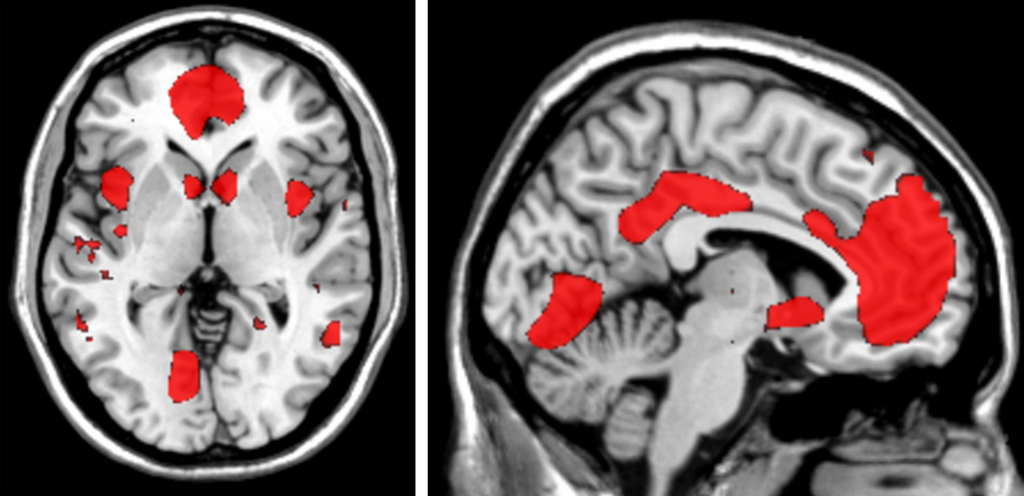

<strong>MEMORY IS REALLY</strong> complicated: This fMRI data from the Stanford Memory Lab shows the numerous areas of the brain (from two different angles!) that are recruited during successful memory retrieval.

We set up the MRI to optimize our ability to measure whats happening in the hippocampus, an area of the brain thats critical for memory, says Trelle, the studys lead postdoc. We can actually see very distinct neural signatures when people successfully remember versus when they forget.